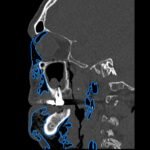

Subcutaneous emphysema (SE) is a rare but significant complication following dental procedures characterized by the presence of air in the subcutaneous tissue. This case report presents a 67-year-old male who developed right-sided facial swelling after tooth extraction, a procedure executed with high-power dental tools. Clinical findings included facial swelling and crepitus with no lip involvement, differentiating SE from an allergic reaction and hematoma. Diagnostic imaging through computed tomography (CT) and chest X-ray confirmed SE, showing diffuse subcutaneous air in facial and neck soft tissues. Initial management in the emergency department (ED) involved administration of antihistamines, corticosteroids, antibiotics, and otolaryngology (ENT) consultation with close monitoring for airway compromise. This case underscores the importance of including SE in differential diagnoses for post-dental procedure swelling, the effectiveness of CT imaging in SE identification, and the importance of early detection and treatment to prevent severe complications like respiratory and cardiac issues.